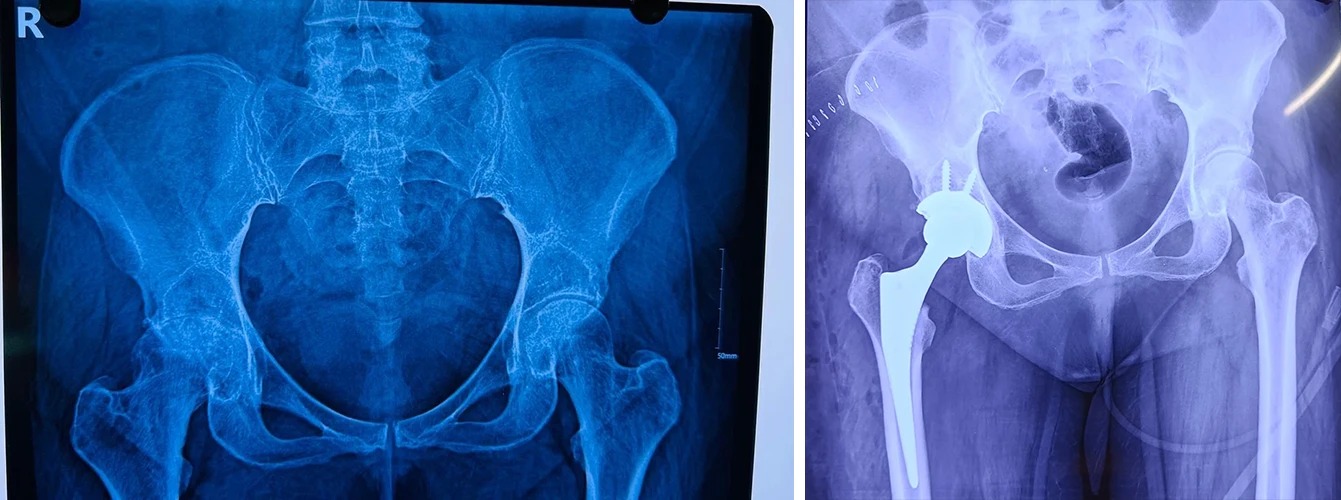

Total Hip Replacement

Are your hips causing you constant discomfort? If you're tired of living with hip pain, Dr. Prasun Sanyal is your best solution.